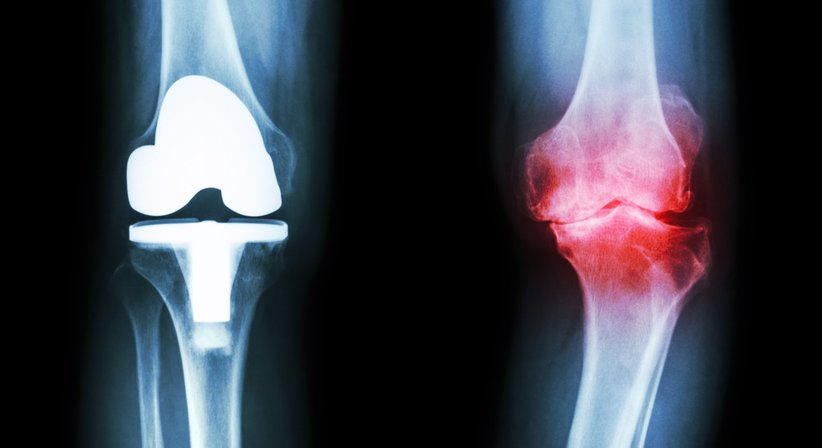

Eine Knieprothese bzw. ein künstliches Kniegelenk ist dann indiziert, wenn das eigene Knie verschlissen und abgenutzt ist. In über 90% der Fälle ist eine schwere Kniegelenksarthrose (Gonarthrose) der Grund für den Einsatz des künstlichen Gelenks.

Bei einer sogenannten Knie-TEP wird das gesamte Gelenk durch spezielle Oberflächenimplantate ersetzt. Der häufigste Grund einer Knietotalendoprothese ist der komplette Verlust des Gelenkknorpels.